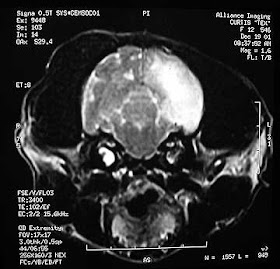

diagnóstico se determina mediante un examen físico y neurológico completo y / o

avanzado de imagen (resonancia magnética o tomografía computarizada).